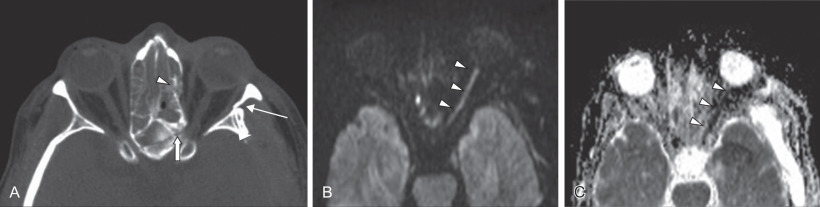

Advantages of MRI include noninvasive imaging without ionizing radiation, and soft tissue resolution in multiple planes that is superior to computed tomography ( Figs. 1.2.9 and 1.2.10 ). In the setting of craniomaxillofacial trauma, MRI can be used to evaluate the optic nerve for traumatic optic neuropathy (TON) ( Fig. 1.2.11 ), as well as herniation of orbital contents into the adjacent maxillary sinus or traumatic encephaloceles. A study by Freund et al. demonstrated that MRI showed the inferior rectus muscle to be herniated through the orbital floor fractures twice as often as when compared to the evaluation of the orbital contents using CT. Although MRI is suboptimal in assessing cortical bone given the paucity of hydrogen atoms, it can depict bone marrow edema associated with chronic complications of trauma such as mandibular osteomyelitis, ischemic necrosis of the condylar head, and traumatic damage to the articular disc. The disadvantages of MRI include high cost, long scan times, metallic hardware that can obscure adjacent structures, and other relative contraindications to MRI.